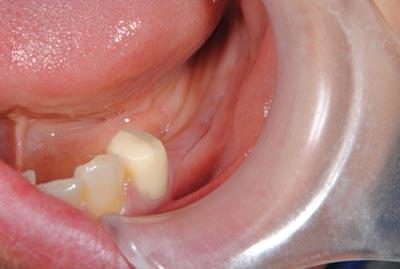

下の写真ですが、上顎前歯2本のうち向かって右の歯がインプラントなのですが、歯肉がわずかに上にあがってしまい、全くの左右対称にはできずに、右の歯の方が少し長くなってしまっています。

1歯35万円(税込38万5000円)のわけ

これなどは、もう少し長くなっていますが、口唇を上に引っ張らない限りはそれが見えません。

以下も、一見それほど問題にならない程度には仕上がっていますが、隣の歯との間、歯肉の間に空間が残っており、中にはご満足いただけないこともあります。幸いにして、この患者様方には、あらかじめ、見た目についてのご説明をさせていただいた上で、治療を始めていますので、ご納得いただいております。